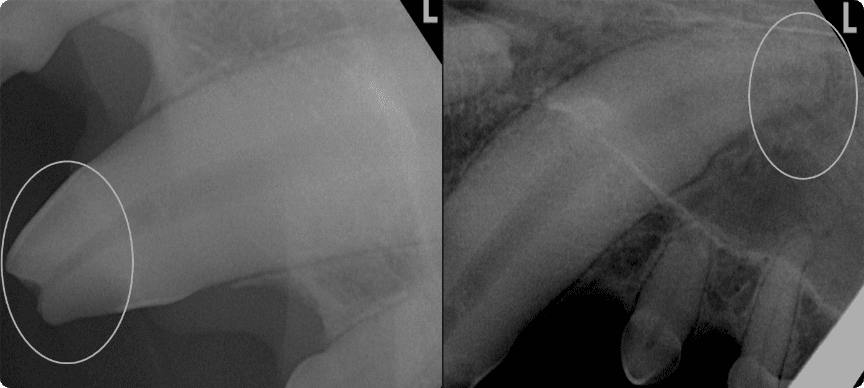

육안으로는 확인이 어려운 잇몸 아래, 치아 뿌리 및 턱뼈의 병변을

치과 방사선으로 진단

치수 감염 또는 심한 치주염으로 인해

치아 뿌리 끝에 고름주머니가 생기는 질환.

심해질 경우, 눈 밑 병변이나 턱뼈의 골절 유발 가능